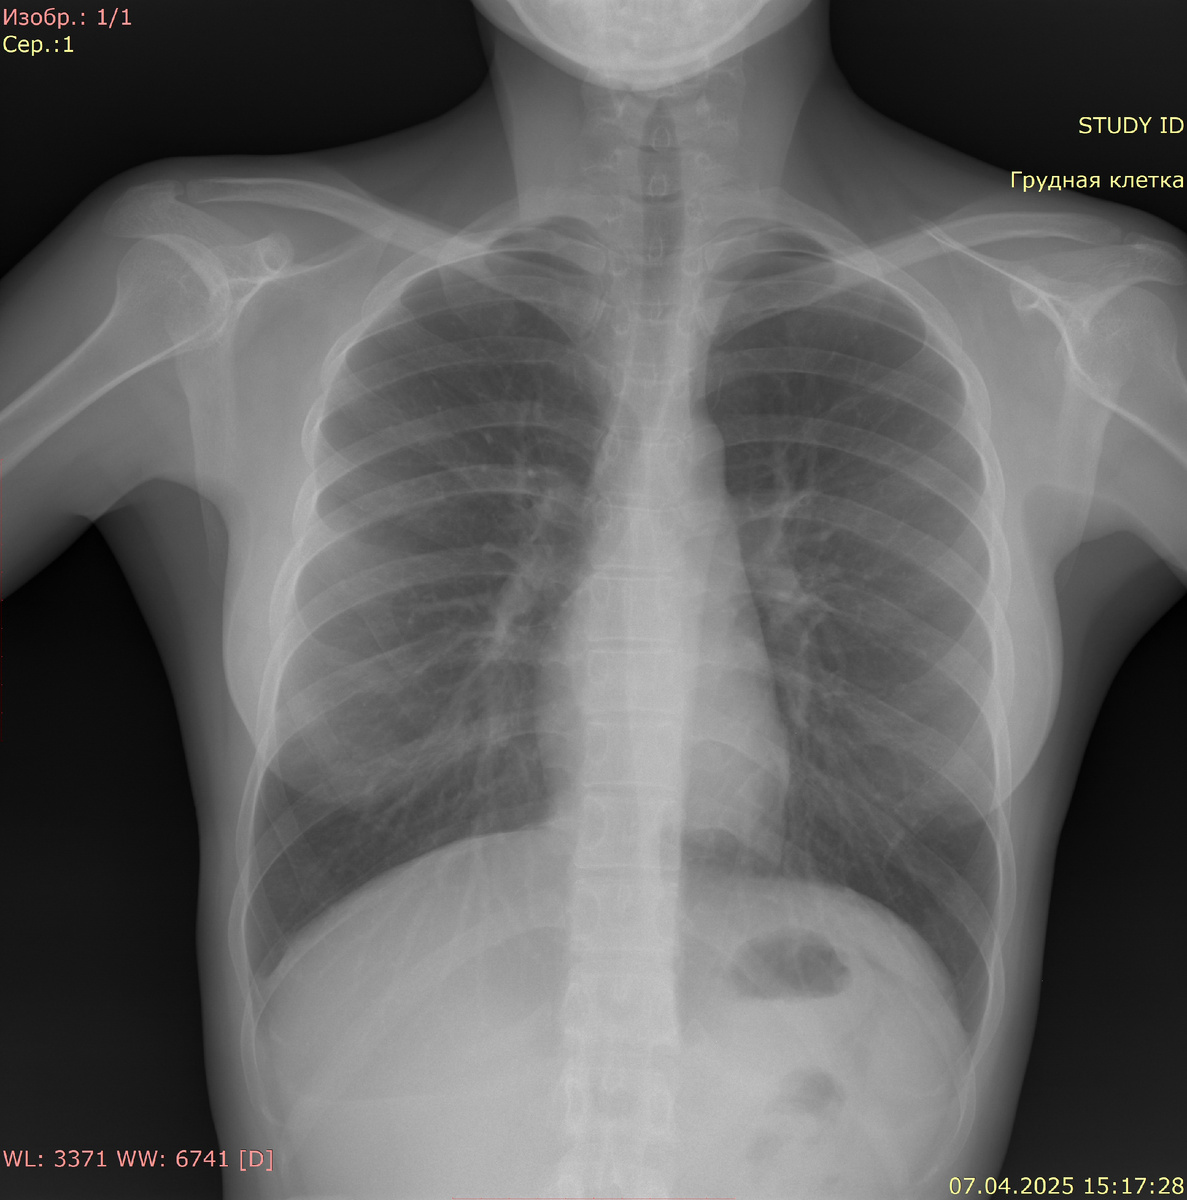

Видимые дыхательные пути проходимы. Тень средостения не смещена, не расширена. Корни легких четкие, структурные, не расширены. Очаговых и инфильтративных изменений в легких нет. Синусы свободны. Расщепление грудинного конца 5 и 6 ребра справа. Свободный газ не определяется.

Заключение: данных за очаговые или инфильтративные изменения не выявлено. Раздвоение 5 и 6 ребра справа (ребра Люшка)